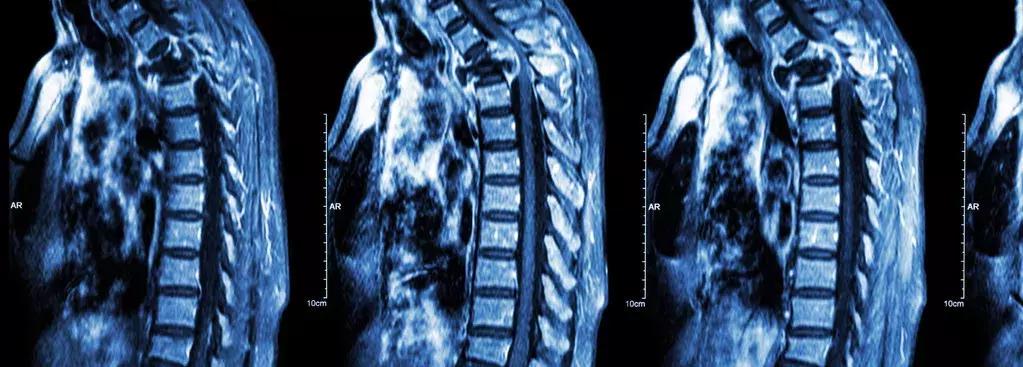

对于脑和脊髓的立体图像,MRI检查的更为全面,且多角度成像不容易漏掉病变部位。另外,核磁对于胆道系统成像也有其先天的优势,因为胆道内流动着胆汁,有“水”的地方就有大量“氢原子”,也是MRI成像的基础,所以判断肝胆系统的疾病,MRI也有一些CT做不到的优点,两者互为补充。但对于骨骼外伤、肺部病变等,CT是更好的选择。建议大家还是遵从医生的建议,进行适合自己病情的检查。